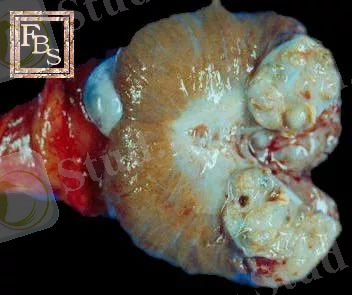

Сыртқы түрі. Сыртқы түрі бойынша ісіктер сан алуан. Ісік домалақ немесе сопақ пішінді болуы мүмкін. Бұл әдетте қатерсіз ісіктер. Сонымен қатар ісіктер емізікше, саңырауқұлақ тәрізді және ағаш тәрізді формаларға ие, ал беткейі тегіс, кедір-бұдырмалы болуы мүмкін. Ісіктің кейбір тілімдері балық етін еске түсіреді(саркомалар), ал басқалары - талшықты құрылым(фибромдар), үшіншілері әртүрліүлкен көлемдег шұңқырға(кистоаденомдар) айналады. Тері ісігі, әдетте, саңырауқұлақ тәрізді формаға(фунгозды) айналады. Терінің бетінде пайда бола, олар талшық тәрізді немесе түсті қырыққабат(қарашық ісіктер) кескініне келуі мүмкін. Сыртқы пішіні бойынша ісіктерді қатерлі немесе қатерсіз екенін ажыратыруға болады. Әдетте қатерсіз ісіктер ағзаның бетінде немесе терінің, қатерлі ісіктер керісінше терініңішінде қалыптасады.

Түсі. Ісік әртүрлі түсте болады. Әдетте, ісік айналасындағы ұлпалардан ақ, сұр немесе сарғыш түспен ерекшеленеді. Ісіктің түсі ісінген ұлпа түріне және тамырлардың өсу дәрежесіне байланысты. Аденоманың түсі бүйрек үсті безінің(мүше түсі) қабығындағы меланомға, меланиндегі пигменттің мөлшері -қара немесе қараңғы - қоңыр түске байланысты. Қатты дамыған тамырлы жүйе ісікке ашық-қызыл рең береді. Егер, ісікте некроз дамыса, онда мұндай аумақтар сұр, сарғыш-жасыл түс, қан кетуде - қызыл немесе қызғыш-қоңыр түске айналады

Консистенциясы . Ісіктердің консистенциясы, әртүрлі және тығыздан жұмсаққа және желетәрізді болады. Ол торшадағы ісік түріне, строманың, тамырлардың өсу дәрежесіне, сонымен қатар, екіншілік дистрофиялық үрдістерге байланысты. Сүйек және шеміршек ұлпаларында болатын, остеомдар, хондромдар, аралас ісіктер - қатты. Тамырлы ісіктер, липомдар, миксомдар, аденом және т. б. - жұмсақ. Ісікті тілген кезде сұйықтыққа немесе шырышқа толы шұңқырды, сонымен қатар, шашылыңқы массадағы аумақтар - некроздарды байқауға болады.

Аденома - безді ағзалар эпителиінен, олардың өзектерінен өсетін безді ісік. Ол айналасындағы тіндерден жақсы шекараланған, үлкендігі бірнеше миллиметр-ден, ондағы сантиметрге жететін, жұмсақ ісік. Аденомалар өсіп шыққан жеріндегі тіндерге ұқсас құрылымдар түзеді. Егер аденома құрамында эпителийден гөрі дәнекер тін өсуі басым болса, бұл ісікті фиброаденома деп атайды.

Аналық без тератомасына негізінен дермоидтық кисталар жатады. Оны кесіп қарағанда іші шаш, май т. б. тіндерімен толған.